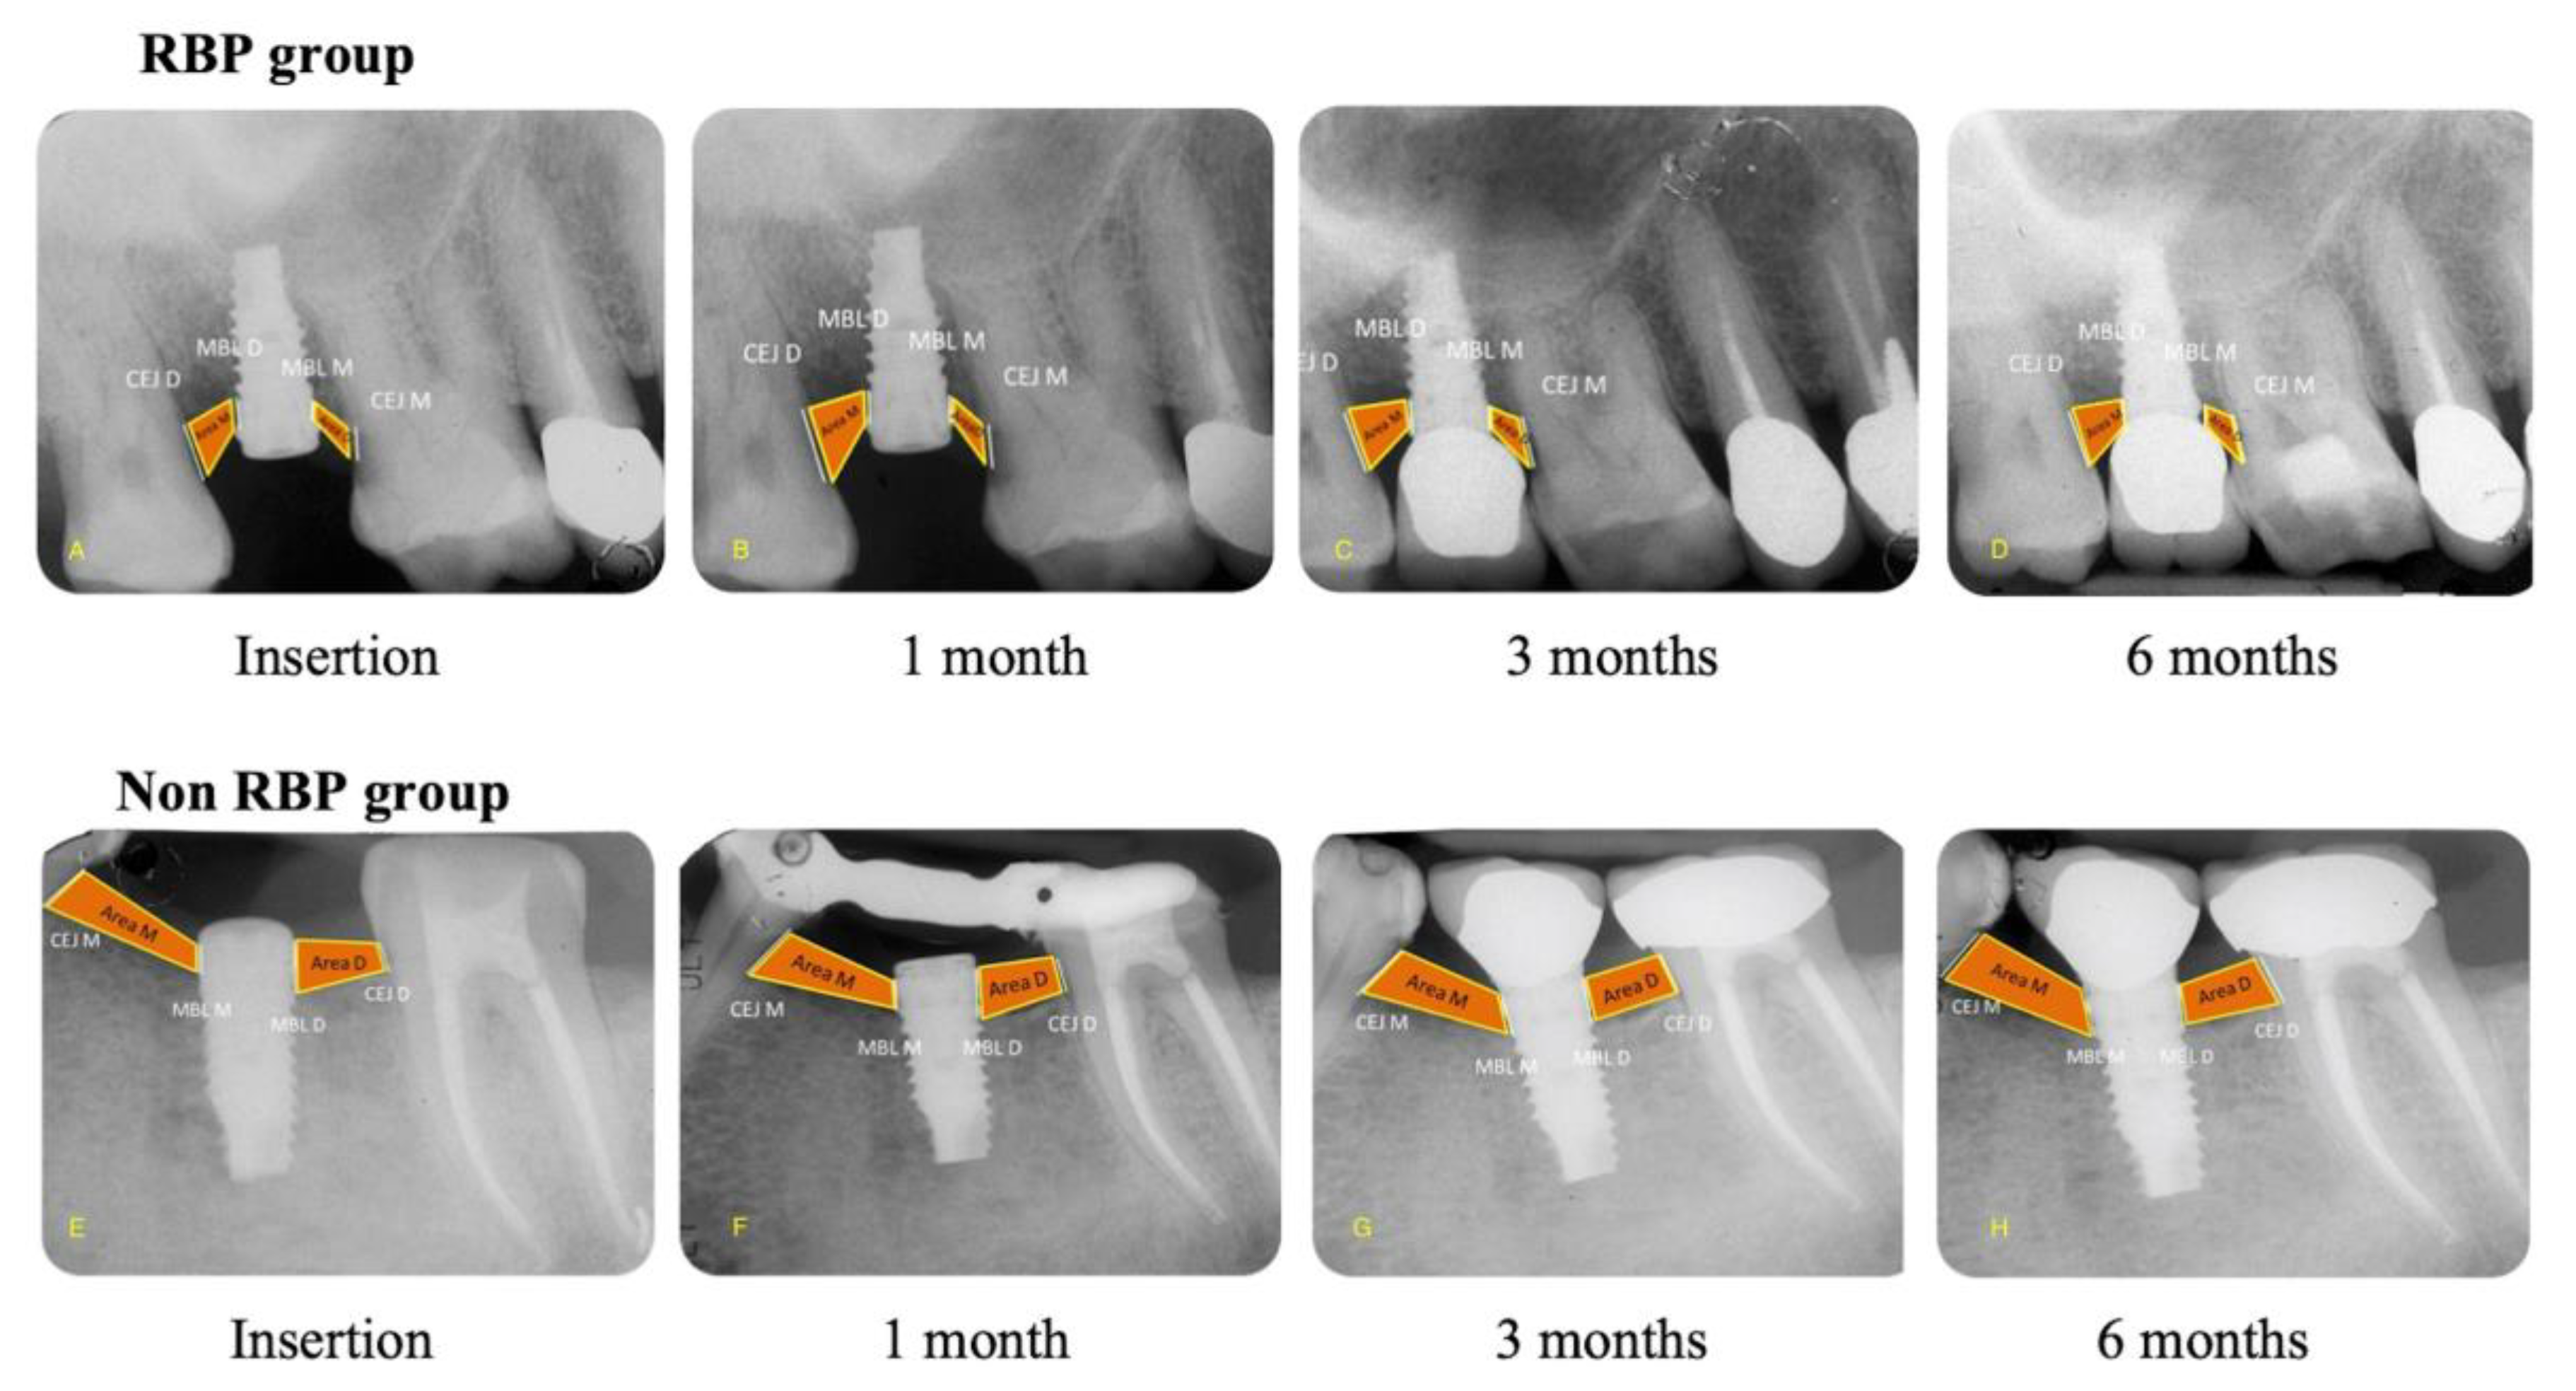

2.9. Radiographic Evaluation

- -

- Mesial and Distal Marginal Bone Levels (MBL-M and MBL-D)

- Mesial and Distal Cement–Enamel Junction (CEJ-M and CEJ-D)

- Mesial and Distal Bone Level Area (Area-M and Area-D)

| MBL-M | 0.03 ± 0.14 aA | −0.18 ± 0.18 aA | −0.01 ± 0.24 aA | −0.36 ± 0.41 aB | −0.07 ± 0.41 aA | −0.70 ± 0.52 aB |

| MBL-D | −0.05 ± 0.17 aA | −0.21 ± 0.26 aA | −0.08 ± 0.23 aA | −0.36 ± 0.45 aB | −0.20 ± 0.40 aA | −0.81 ± 0.51 aB |

| CEJ-M | 0.01 ± 0.29 aA | −0.12 ± 0.29 aA | −0.01 ± 0.40 aA | −0.20 ± 0.35 aB | −0.08 ± 0.61 aA | −0.48 ± 0.47 aA |

| CEJ-D | 0.02 ± 0.24 aA | −0.14 ± 0.22 aA | −0.01 ± 0.29 aA | −0.30 ± 0.25 aA | −0.04 ± 0.46 aA | −0.65 ± 0.36 aA |

| Area M | −0.17 ± 0.05 aA | −0.23 ± 0.16 aA | −0.30 ± 0.06 aA | −0.13 ± 0.28 aB | −0.43 ± 0.14 aA | −0.27 ± 0.32 aA |

| Area D | −0.07 ± 0.09 aA | −0.03 ± 0.20 aA | −0.13 ± 0.13 aA | −0.16 ± 0.33 aA | −0.35 ± 0.10 aA | −0.16 ± 0.38 aB |